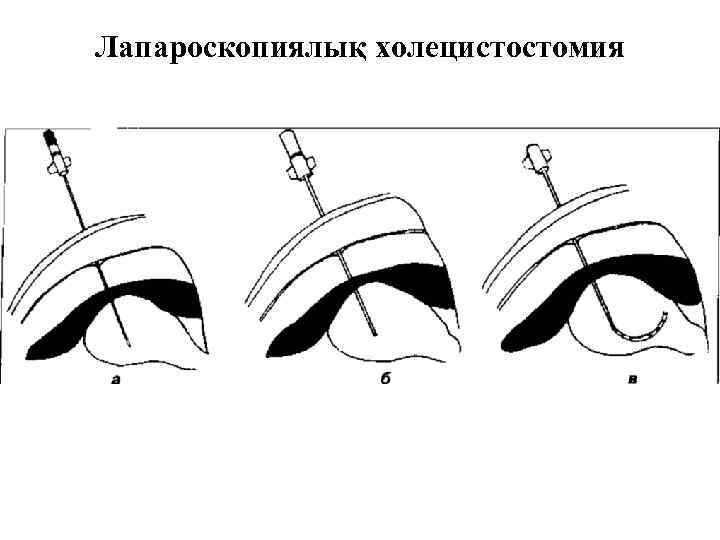

Лапароскопиялық холецистостомия